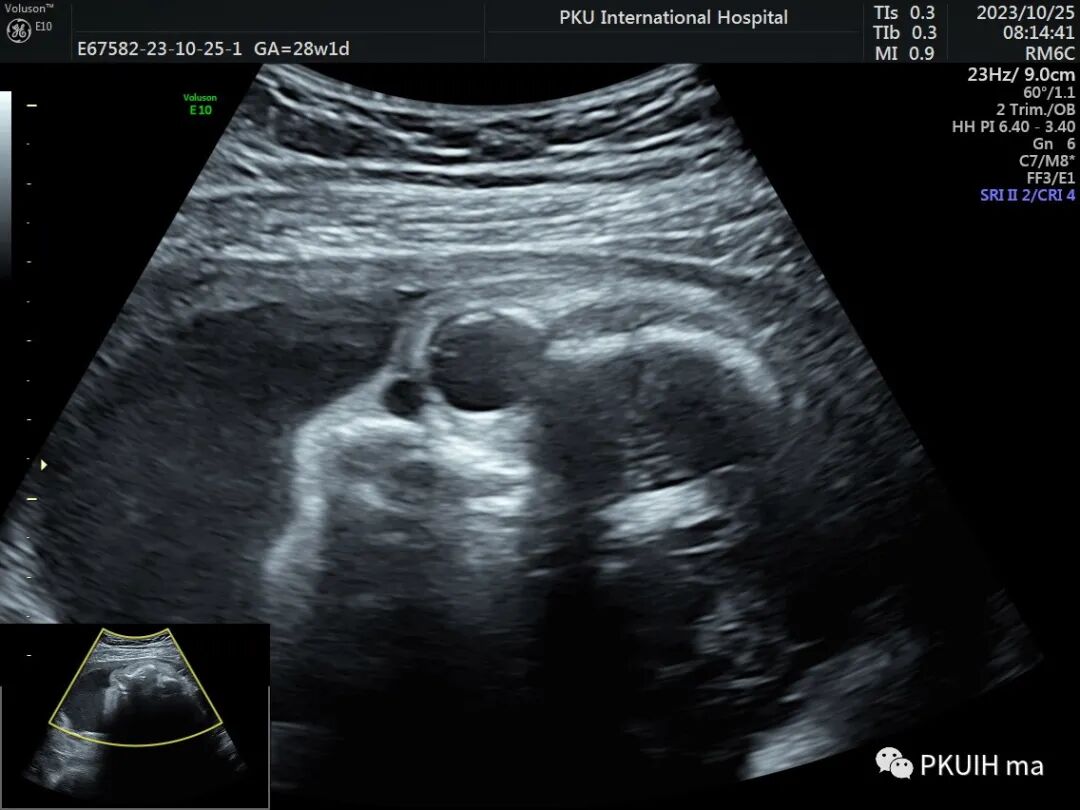

在晚孕期超声经常能发现胎儿眼眶内下方鼻旁处有小的无回声区,可以双侧也可以单侧,这种是非常常见的胎儿鼻泪管囊肿。

鼻泪管囊肿一般在孕晚期常见,多数在自动消失,主要是由于鼻泪管远端堵塞所致。最常见的是近Hasnei瓣外的一层黏膜阻断导管,引起鼻泪管囊状扩张,从而形成囊肿。超声表现为眼内下方鼻骨旁见圆形或类圆形无回声,大小一般小于1cm,内透声良好。随孕周增加超声复查可以消失或变小,极少部分至足月分娩时仍可见。